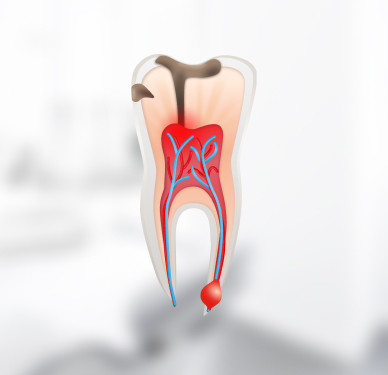

Кариес – самое распространённое заболевание полости рта. Без своевременного лечения оно приводит к пульпиту. Основные симптомы кариеса — потемнение эмали и появление углублений, повышенная чувствительность зубов к горячему и холодному, неприятный запах изо рта. Игнорирование этих симптомов может стать причиной потери зуба или его дорогостоящего лечения.

В клинике «Новая Орбита» вы получите квалифицированную помощь в лечение любых заболеваний полости рта: кариеса, пульпита, периодонтита и других. Проводим лечение без бормашины и с минимальным травматизмом. Проверенная европейская анестезия подбирается строго с учётом индивидуальных показателей пациента.

Мы делаем всё возможное, чтобы сохранить поражённый зуб, избежать необходимости дальнейшего протезирования или имплантации.